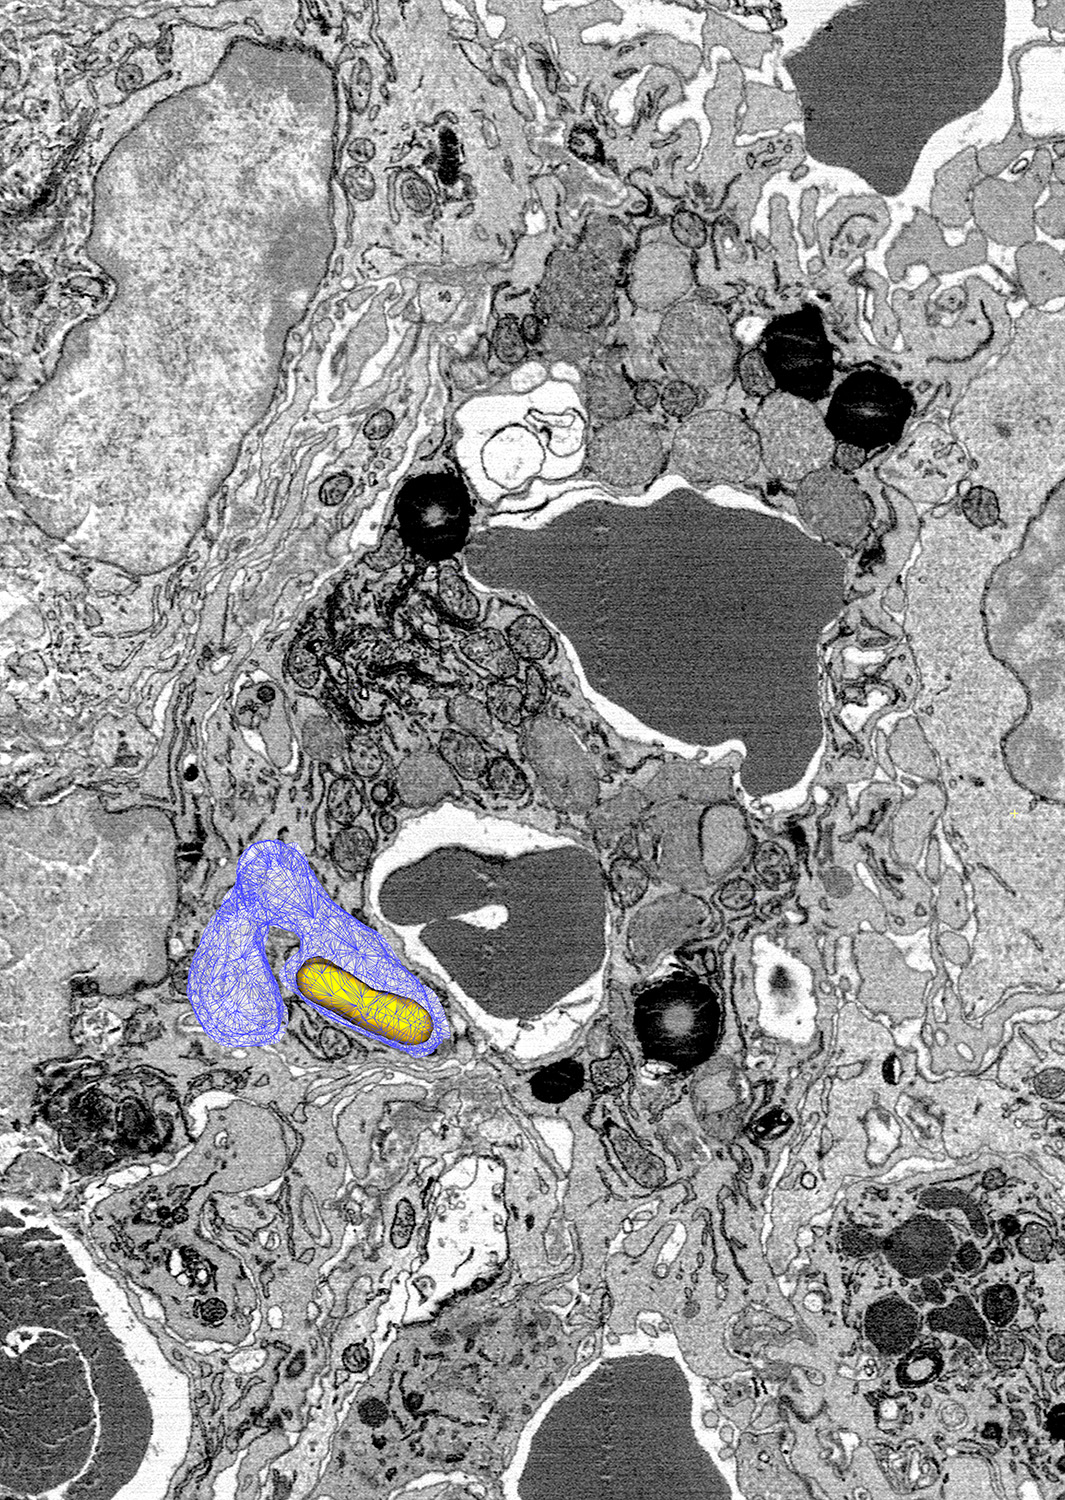

«Wir haben in den Makrophagen der Milz zwei Populationen von Salmonellen entdeckt. Eine Gruppe lebt in eisenarmen Bereichen und vegetiert dort buchstäblich vor sich hin», erklärt Bumann. «Die zweite Population befindet sich in den Vesikeln, wo die roten Blutkörperchen abgebaut werden.»

Auch dort entfernt die NRAMP1-Pumpe das Eisen, welches dann wieder recycelt wird. Die Menge an Eisen ist dort aber extrem hoch. «Selbst wenn über 99 Prozent des Eisens herausgepumpt werden, reicht die Restmenge den Erregern aus, um sich weiter zu vermehren», so Bumann. Diese gut versorgten Bakterien sind es denn auch, die das Infektionsgeschehen dominieren.